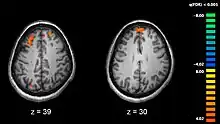

Données neurophysiologiques obtenues par imagerie cérébrale

Avec le développement récent des techniques d'imagerie médicale, beaucoup de travaux sont consacrés à l'étude de différences structurelles ou fonctionnelles dans certaines régions cérébrales chez des personnes schizophrènes par rapport aux individus non schizophrènes.

Le cerveau des personnes avec schizophrénie serait d'apparence globalement normale et seules des techniques récentes d'imagerie cérébrale, utilisées lors d'étude sur des cohortes de patients, ont pu mettre en évidence certaines différences. La première différence structurelle observée fut la découverte d'un élargissement des ventricules cérébraux chez des patients dont les symptômes négatifs étaient particulièrement marqués[160]. Toutefois, ce résultat ne s'avère guère utilisable au niveau individuel, du fait de la grande variabilité observée entre les patients. Un lien entre l'élargissement ventriculaire et une exposition aux médicaments neuroleptiques a cependant été suggéré[161]. Des études plus récentes ont par la suite montré qu'il existe de nombreuses différences dans la structure cérébrale selon que les personnes présentent ou non un diagnostic de schizophrénie[162]. Toutefois, comme dans le cas des études antérieures, la plupart de ces différences ne sont détectables que lorsque des groupes, et non des individus, sont comparés, et ne sont conséquemment pas utilisables pour établir le diagnostic de schizophrénie.

Des études mettant en œuvre des tests neuropsychologiques combinés à des techniques d'imagerie cérébrale comme l'imagerie par résonance magnétique fonctionnelle (IRMf) ou la tomographie par émission de positons (TEP) ont cherché à mettre en évidence des différences fonctionnelles d'activité cérébrale chez des patients. Elles ont montré que ces différences surviennent plus fréquemment au niveau des lobes frontaux, de l'hippocampe et des lobes temporaux[163]. Ces différences sont fortement liées aux déficits cognitifs fréquemment associés à la schizophrénie, notamment dans le domaine de la mémoire, de l'attention, de la résolution de problèmes, des fonctions exécutives et de la cognition sociale.